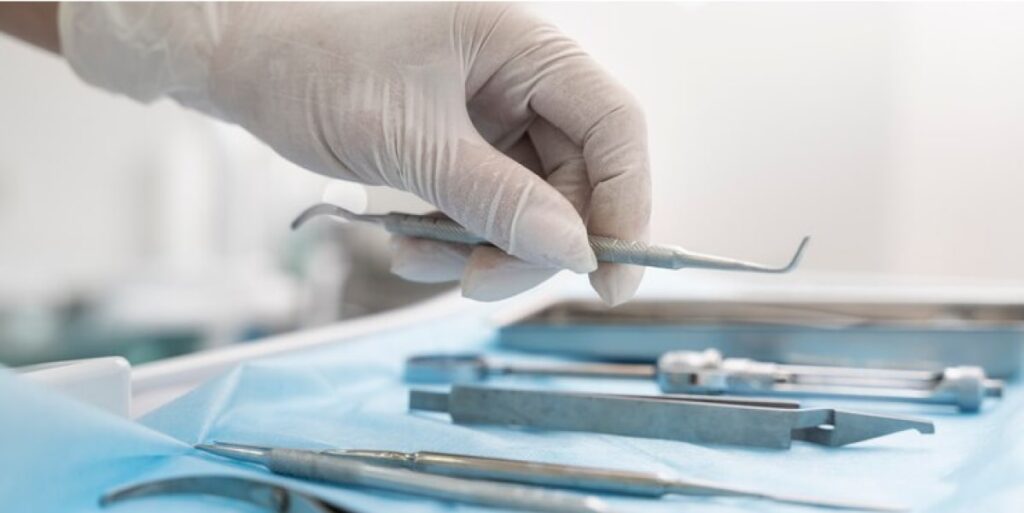

معتبر ترین و مجهز ترین کلینیک تخصصی دندانپزشکی در ایران

Best Dental Office with the Best Tools and Doctors in IRAN